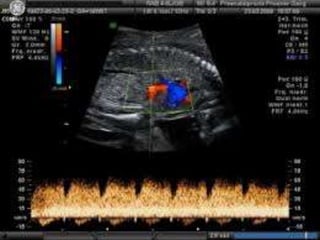

Normal Ductus venosus Blood Velocity

• The ductus has a usually high flow during the

entire cardiac cycle compared to the

neighboring veins.

• Starting the early gestation the velocity

increases to reach a plateau at 22 weeks.

• For the rest of the pregnancy the PSV ranges

between 40-85 cm/s

• The velocity pattern reflects the with a peak

during systole and another during diastole ,

and a nadir during active diastolic filling(atrial

contraction).

• Typically this nadir doesn’t reach zero or

below zero during the second half of

pregnancy.

• However below 15 weeks a nadir zero or

below zero is being recorded in normal

fetuses.